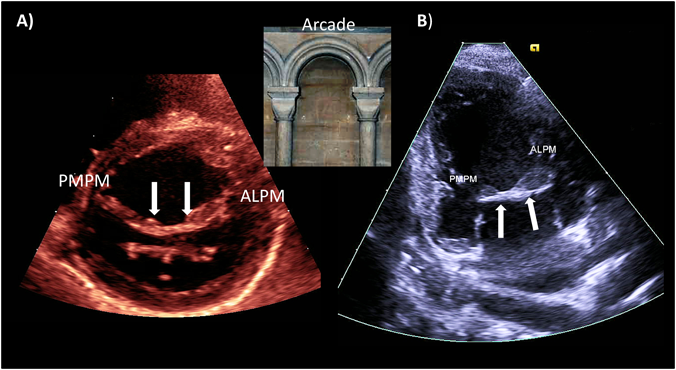

B) 異常僧帽弁架橋(mitral arcade/hammock mitral valve)(Fig. 7)

Pediatric Cardiology and Cardiac Surgery 33(2): 140-156 (2017)

Fig. 7 Mitral arcade

(A) Short axis image of the mitral arcade. (B) Apical two-chamber view of the mitral arcade. Arrows indicate the myocardial bridge between the two papillary muscles. Note the resemblance of the morphology between the mitral valve anatomy and the arcade.

両乳頭筋間が筋線維性の索状構造により架橋している形態を持つことが診断の要となる.この形態がarcadeに似ていることからこの呼び名がある.Hammock mitral valveと同一疾患であるが,現在ではmitral arcadeで呼称が統一されている.腱索が非常に短くしかも癒合・肥厚していることがあり,時には腱索を介さずに弁尖が直接架橋筋束に付着する.乳頭筋も低形成かつ多頭性のことが多く,乳頭筋の低形成が著明な場合には左室壁へ腱索が直接付着する.この場合には弁の可動性が極端に制限され,重度の僧帽弁狭窄と閉鎖不全の両方を合併する13)